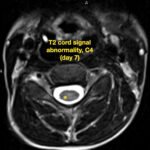

There is a growing body of literature and scientific discovery on pediatric autoimmune encephalitides. This is a heterogenous group of neuroinflammatory conditions leading to often perplexing acute and progressive neurologic and/or neuropsychiatric symptoms. This report demonstrates the evaluation and management of an adolescent with myelin-oligodendrocyte glycoprotein (MOG) antibody-associated fulminant acute disseminated encephalomyelitis (ADEM) in the context of current literature. The featured magnetic resonance imaging uniquely highlights progressive central nervous system lesions detected over the course of the first week of disease.